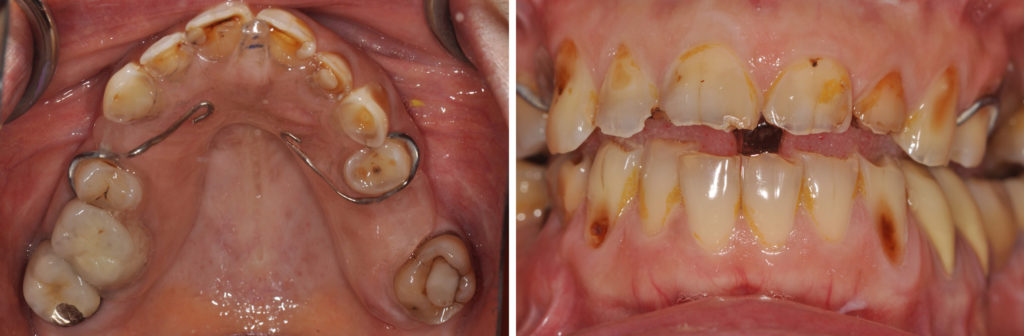

Fig. 8a à 8j : Résultat final

AVANT/APRÈS :